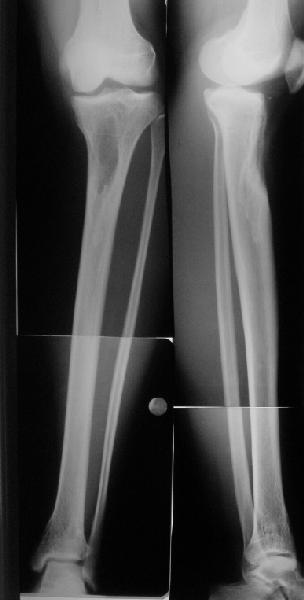

Коллеги из детского отделения направили 18-летнюю студентку с варусно-рекурвационной деформацией проксимального отдела голени.

Жалобы у нее на появившиеся боли в колене при нагрузках. Признаков воспаления не было и нет, опухолевого роста также. Природа дефекта в области бугристости не очень понятна. Дополнительно сделали КТ и боковой снимок в максимальном разгибании - все в приложении.

По-поводу деформации - Вы имеете дело с епи-метафизарной деформацией, скорее всего по причине преждевременного частичного закратия проксимальной зоныы роста большеберцовой кости.

За точку отсчёта при планировании коррекции надо взять латеральный снимок в максимальном стрессе на разгибание. Остеотомию необходимо произвести тот час дистальнее места прикрепления собственной связки надколенника.(очень важно)

Для точных расчётов необходимо сделать снимки двух ног прямые и боковые на всю длину от тазобедренных суставов до стоп.

Ориентировачно на боковой проекции угол между тибиальным плато и анатомической осью тибии на передне-боковой проэкции должен быть порядка 90 градусов, а на боковой 80, кроме того на боковой проэкции при выпрямленном колене передний кортекс большеберцовой кости должен находиться на одной линии с передним кортексом бедренной кости.